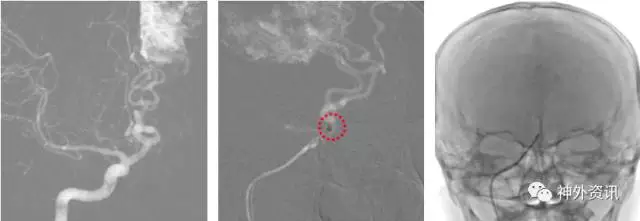

(DSA:烟雾病;左侧大脑后动脉P2段夹层动脉瘤)

(左:Envoy DA导引导管-右侧椎动脉V3段;右:支架导管成功超选左侧大脑后动脉)

(支架辅助弹簧圈栓塞-动脉瘤不显影,载瘤动脉通畅)